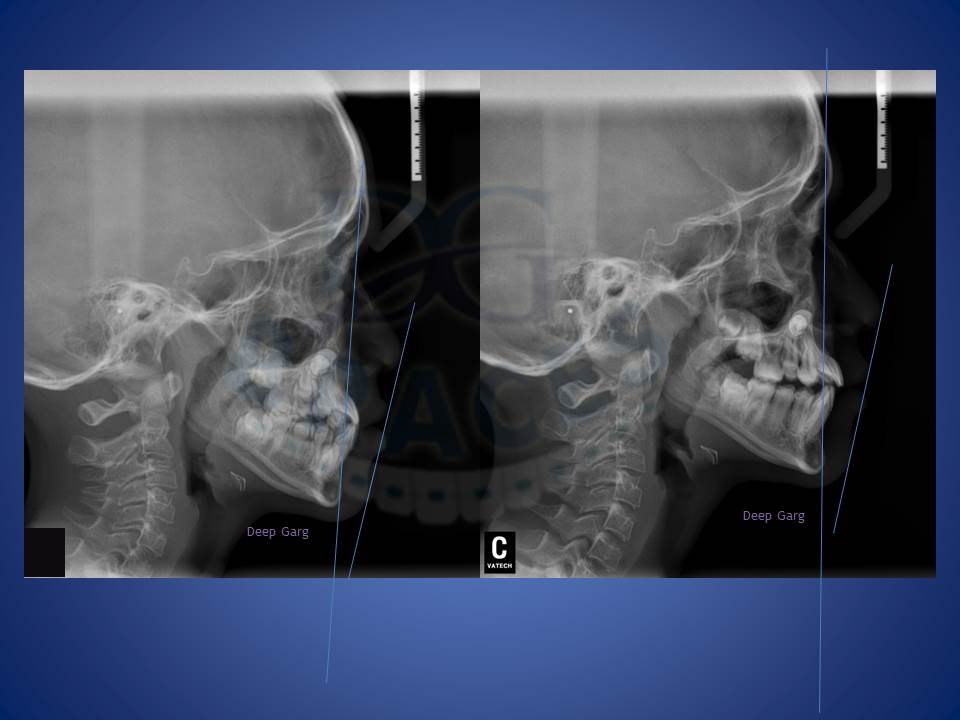

6.Lower jaw when forward can be corrected with the help of reverse pull head gear when treated at young age of 12-14 in boys and 10-12 yrs in girls. excellent result achieved here!!!